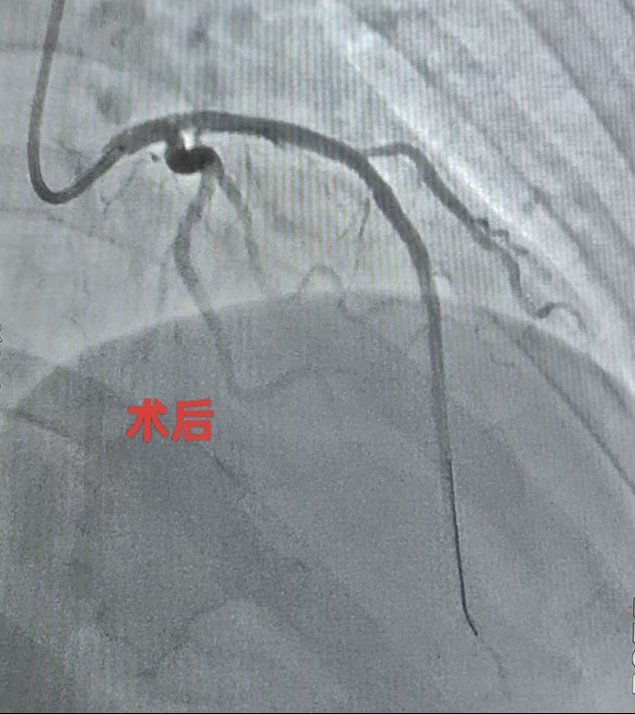

听说要做心脏手术,王女生十分紧张,“总感觉自己得了大病”。魏望江便亲自前去劝解。为了让患者安心,同时确保第一例心脏介入手术顺利开展,魏望江特意邀请北京地坛医院心内科副主任(主持工作)管浩等人讨论病情,在管浩主任的指导下,根据患者情况制定合理的手术和治疗方案。4月16日,由北京地坛医院董茜、郑迪两位专家主刀,徐州医院导管室医护人员参与,为王女士行心脏冠状动脉造影及支架置入术。术后患者恢复良好,无并发症,各项检查指标均在合理范围,即将办理出院。

(术前术后冠状动脉对照)